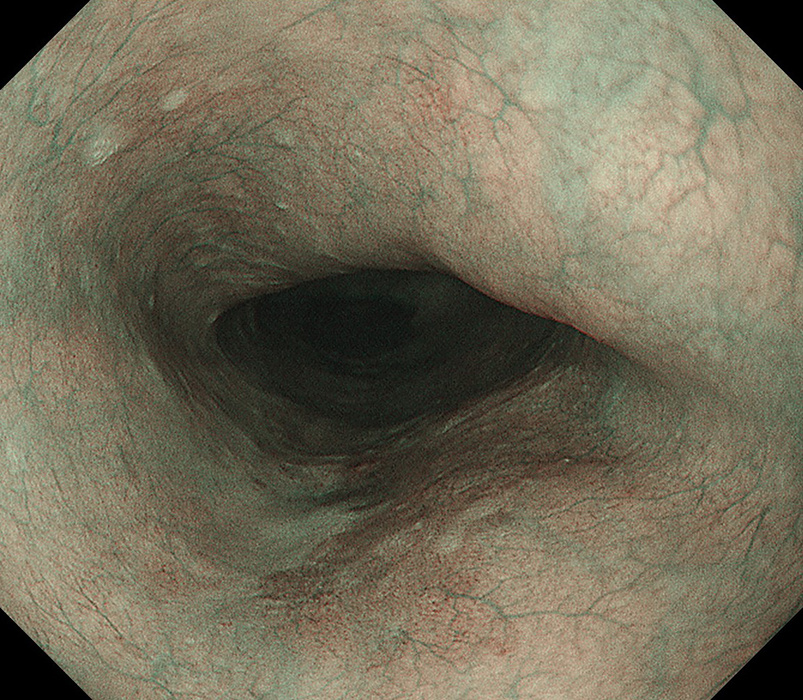

内視鏡検査イメージ